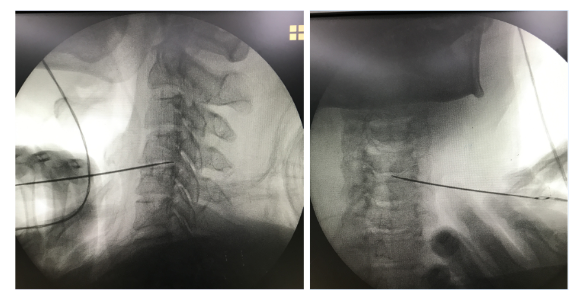

3、微创手术治疗:

如果经上述治疗效果不理想,可考虑行经皮激光椎间盘减压术、臭氧消融术或者经皮穿刺椎间盘低温等离子髓核成型术等,该治疗方式通过去除部分髓核组织,减轻病变椎间盘的压力,从而缓解神经根及椎间盘周围痛觉感受器的刺激,消除和缓解临床症状。